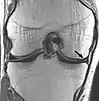

Musculoskeletal

Applications in the musculoskeletal system include spinal imaging, assessment of joint disease, and soft tissue tumors.[38] Also, MRI techniques can be used for diagnostic imaging of systemic muscle diseases including genetic muscle diseases.[39][40]